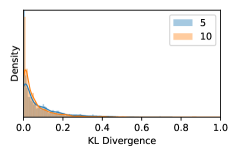

Kullback-Leibler (KL) Divergence Metric (kl) Similar to the variance metric, the KL divergence metric [21] measures the deviation of individual learner’s predictions from the ensemble output . The uncertainty score of input under the KL divergence metric can be written as This metric will be later referred to as kl.

A problem with var and kl is that they focus mainly on the disagreement among ensemble predictions but do not take in consideration the value of . Consider a scenario where the all ensemble members predict a probability of . Both var and kl will produce an uncertainty score of and thus will not be able to capture any decision uncertainties; in fact, this case where all learners give an output of is highly uncertain.

Uncertainty Scores on Out-of-Distribution Datasets As an additional experiment, we also tested the performance of the ensemble models on o.o.d. data inputs, which is a classic application of prediction uncertainties [1]. For this task, we produced distribution plots similar to those in Figure 4 for the previous experiment in our supplementary materials. The visualizations for the two o.o.d. image datasets can be found in Figure S.5 for ImageNet and in Figure S.6 for CIFAR-10. The results showed that the majority of o.o.d. data received higher uncertainty scores than in-distribution data for all three ensemble methods, suggesting that these ensemble methods would indeed perform well on o.o.d. detection tasks.

As discussed in Section 5.1 and Section 5.3 in the main paper, the mean metric and the stacking ensemble will have better performance in the precision (specificity) on the ambiguous data. Here, more detailed results are shown in Figures S.3 & S.6 and Table S.1. Figures S.3 & S.4 show the histograms of the uncertainty score for Kaggle-DR and Messidor-2 datasets that are the in-distribution (i.d.) dataset in our experiment and FigureS.5 & S.6 show the histograms for ImageNet and CIFAR-10 datasets, which is the o.o.d. datasets in our experiment. Each group of histograms contains results from the three evaluated ensemble methods (stacking ensemble, MC-dropout and TTA) and the three uncertainty metrics (mean, var and kl). Additional detailed results not displayed in Figure 4 can be found in Table S.1, which shows the proportion of the data of different SLs varies across different . For comparison, we also included in Table S.1 the results from single learners, and the proportions of data of different SLs (before any selection was made).